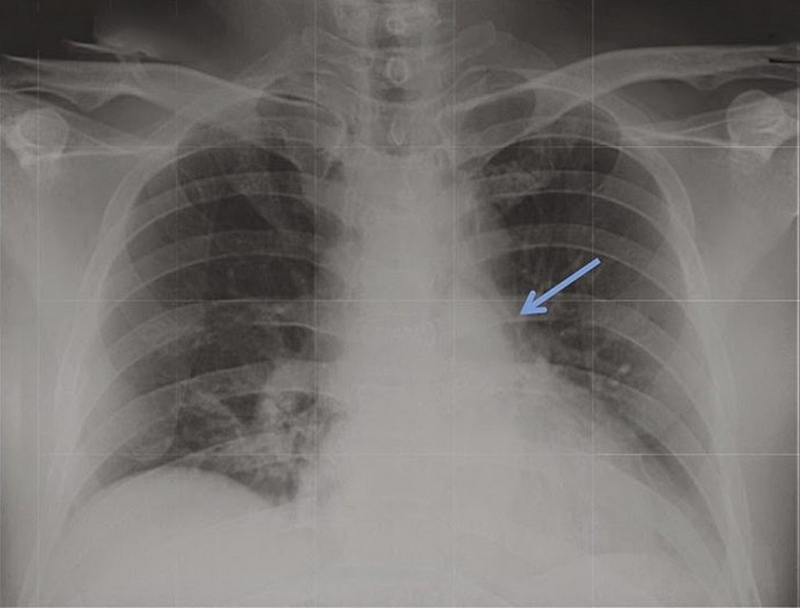

Tràn khí trung thất là khi có sự xuất hiện của không khí hoặc bất kỳ loại khí nào ở khoang trung thất. Trong đó, khí có thể rò rỉ vào trung thất theo 3 cơ chế sau:

Đừng quá lo lắng khi bị nghi ngờ có khí tự do trong trung thất, hiện nay có nhiều biện pháp để quản lý hiệu quả tình trạng này. Trước tiên, bác sĩ sẽ tiến hành thăm khám lâm sàng và chỉ định người bệnh thực hiện một số xét nghiệm gồm: